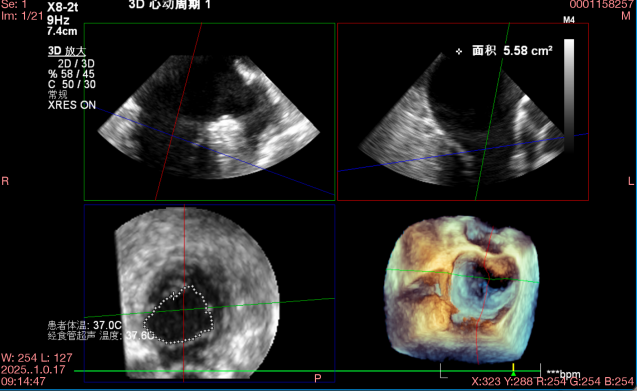

术前心超提示:

退行性二尖瓣反流(DMR),A2-A3脱垂伴连枷样运动(脱垂范围:17mm,连枷间距:7mm),P3脱垂,反流主要位于2-3区,MR重度4+(VC:6*17 mm),A3:18mm,P3:9mm,A2:24mm,P2:14mm,AP:32mm,二尖瓣口面积MVA约 5.6cm²,左房、左室明显扩大。

术中操作(关键步骤超声)

在全麻下,于心尖入路完成ValveClamp®装置植入。术中多学科团队密切配合,超声全程实时指导操作。最终,于2偏3区成功植入一枚Ⅲf夹子,一次夹合完成。前叶夹合量12mm,后叶夹合量10mm,反流降至1+,导管操作时间30分钟。术后平均跨瓣压差3mmHg。